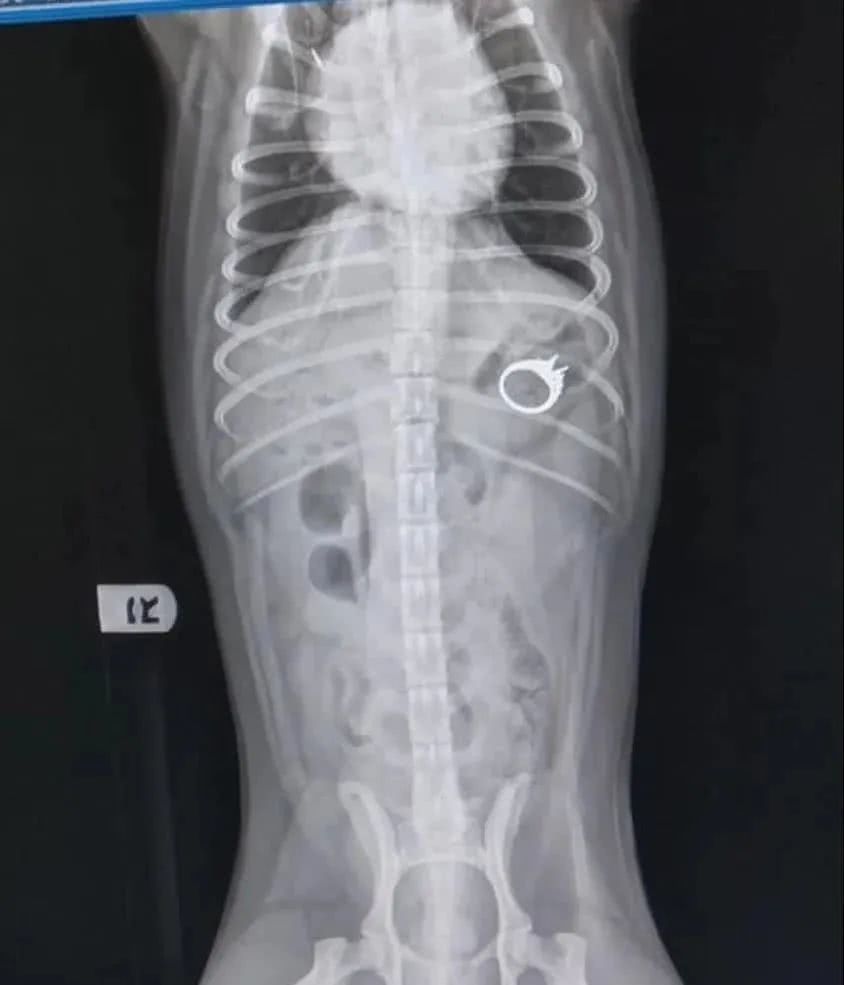

女子过去一看的确是自己的钻戒,然而当她准备去拿的时候,狗竟然将钻戒吞进了肚子里。女子便立马带上狗去医院看看该怎么办。

X光显示钻戒已经到了狗狗的胃肠道内,并且这钻戒棱角分明可能会威胁到狗狗的生命安全,于是决定手术取出。好在一切都挺顺利的。

但是当女子看到了手术账单后,顿时十分心塞没话说了,甚至有点儿想哭,因为竟然要支付1万6,这到底是钻戒身价涨了,还是狗的身价又涨了呢?